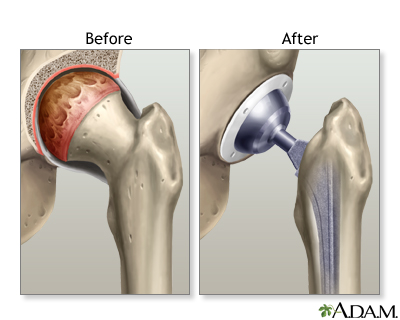

Hip joint replacement is surgery to replace all or part of the hip joint with a man-made joint. The artificial joint is called a prosthesis.

Your hip joint is made up of 2 major parts. One or both parts may be replaced during surgery:

- The hip socket (a part of the pelvic bone called the acetabulum)

- The upper end of the thighbone (called the femoral head)

The new hip that replaces the old one is made up of these parts:

- A socket, which is usually made of strong metal.

- A liner, which fits inside the socket. It is most often plastic. Some surgeons are now trying other materials, such as ceramic or metal. The liner allows the hip to move smoothly.

- A metal or ceramic ball that will replace the round head (top) of your thigh bone.

- A metal stem that is attached to the thigh bone to anchor the joint.